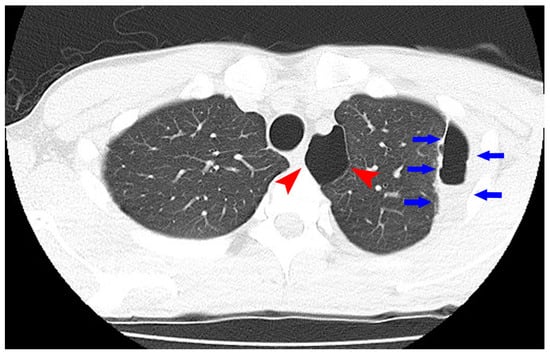

To maintain the remission, 20 mg/day of TOF was continued. His general condition improved, and discharge was considered. Suddenly, on the 29th day of hospitalization, he developed fever and chest pain. Serum C-reactive protein level was markedly increased. Suddenly, he developed fever and chest pain on Day 29. Serum C-reactive protein level was markedly increased. Computed tomography (CT) of the chest showed an emphysematous bulla in the upper left lobe of the lung and fluid formation inside the bulla (Figure 2). He was diagnosed with lung abscess by a pulmonologist and was started on meropenem. Table 2 shows the patient’s laboratory data at the onset of lung abscess. TOF was discontinued. The treatment was successful, and the imaging findings improved. He resumed TOF on Day 37 of his hospital stay and was discharged on Day 42. At present, his remission is maintained with continued with TOF alone, and he has not experienced any adverse event, including a relapse of the lung abscess. The patient’s clinical course is shown in Figure 3. One year after being treated with TOF alone, the endoscopic findings of mucosal inflammation had improved (Figure 4 A,B).

Figure 2. Computed tomography of the chest showed an emphysematous bulla (Arrowhead) in the upper left lobe of the lung and fluid formation inside the bulla (Arrow).

Generally, while discontinuing PSL administration in a patient with refractory PSL, it is necessary to withdraw PSL gradually. Therefore, the next immunosuppressive agent should be administered before PSL is withdrawn, resulting in a period of time where two drugs are used together. In our patient, a lung abscess developed in the duration where both PSL and TOF were being consumed. However, after PSL withdrawal and during remission maintenance treatment with only TOF, no serious infection, was observed. Thus, in our case, it was considered that the lung abscess was caused by excessive immunosuppression due to the combination of PSL and TOF. In addition, our patient had an emphysematous bulla that presented a risk for lung abscess. Therefore, the presence of the bulla might have propounded the development of the lung abscess under excessive immunosuppression.